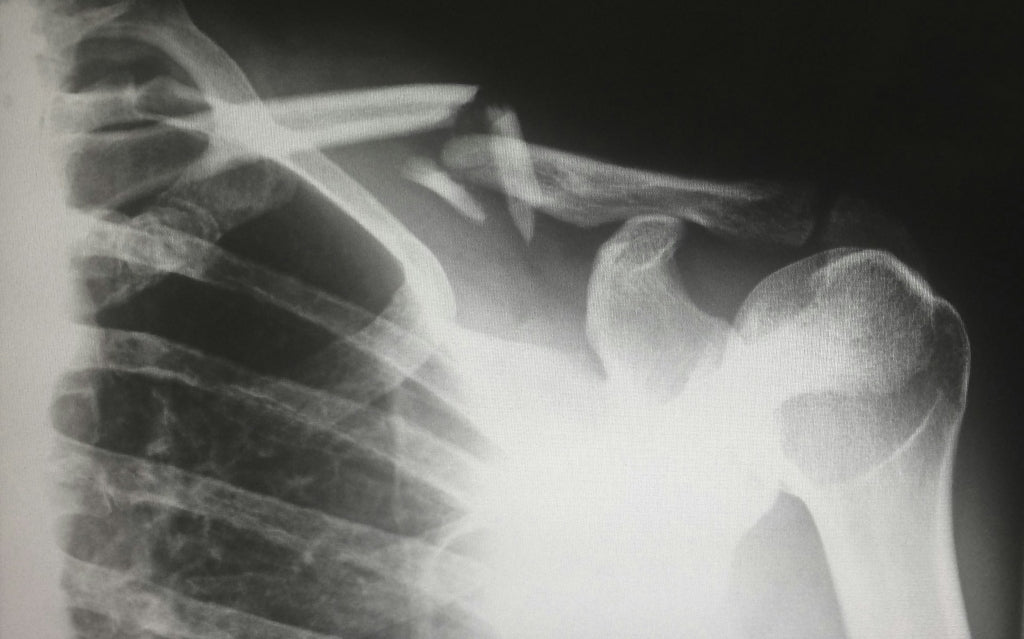

Bei Osteoporose ähnelt die Knochenstruktur einer Bienenwabe mit vergrößerten Löchern, wodurch die Knochen anfälliger für Brüche werden. Weltweit sind Millionen von Menschen von dieser Krankheit betroffen, und jährlich ereignen sich mehr als 8,9 Millionen Knochenbrüche aufgrund von Osteoporose [2].

✅ Unerklärte Frakturen (Knochenbrüche), insbesondere nach nur leichten Stürzen oder Stößen [3]